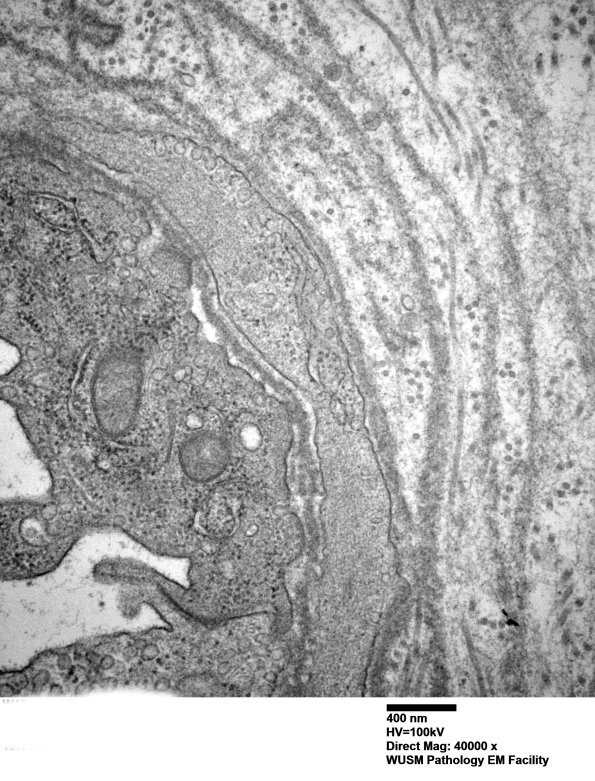

The endoneurial vessels show thickening by concentric proliferation of basal lamina. (electron micrographs) ---- Interpretation: This non-diabetic patient shows a pattern associated with diabetes and, instead, exhibits C5b-9 deposition on the endoneurial vasculature, a pattern consistent with HIEM.